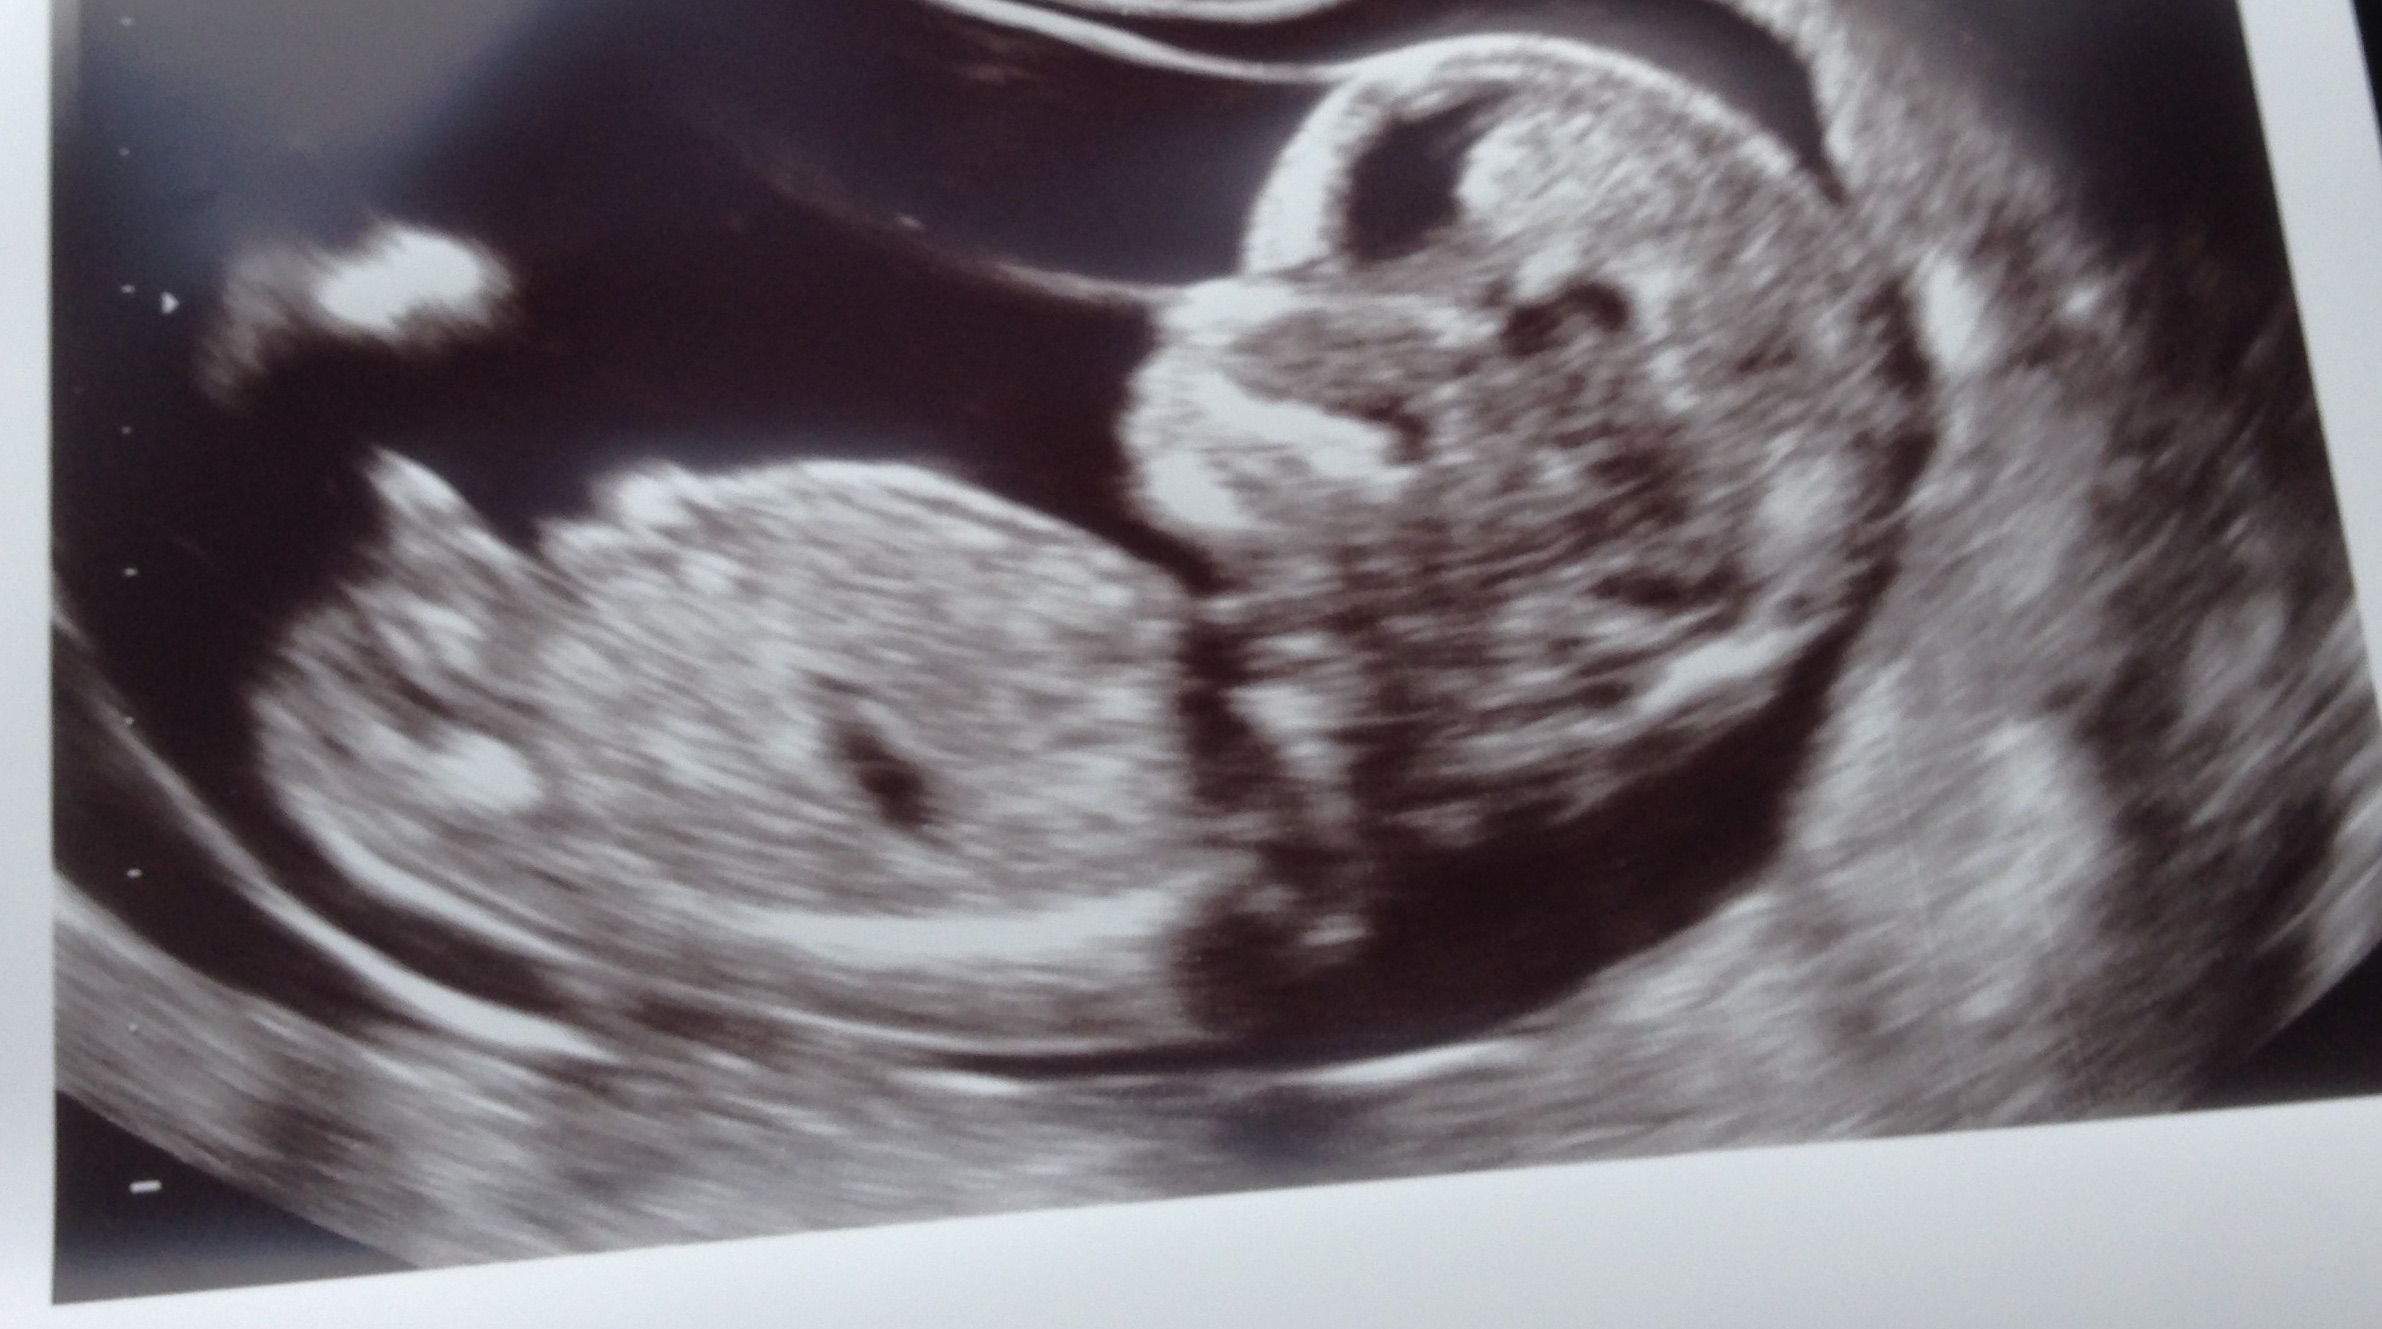

Really need help figuring out boy or girl on 25 week ...

Really need help figuring out boy or girl on 25 week ... from www.thisissesame.com

We had 2 different techs; Discover what your little boy's ultrasound will look like at different stages of pregnancy and learn some interesting facts about the making of a boy. I asked the technician if she could tell the gender and she said that she thinks i am carrying a boy. Any ideas if its a boy or girl? 1668 x 1798 jpeg 257 ะบะฑ. How accurate is an ultrasound at 18 weeks 5 days in determining gender? Ultrasound images of your growing baby boy. 14 week pregnancy ultrasound baby moving and yawning.

Is she spot on or should we wait until around 20 weeks to make sure? 12 week fist trimester screening/nuchal translucency ultrasound. Ultrasound of 12 weeks and 4 days unborn baby boy. I'm so in love lol just out of curiosity what's your opinion of gender? 12 weeks 5 days ultrasound/ gender reveal. Upload, livestream, and create your own videos, all in hd. I asked the technician if she could tell the gender and she said that she thinks i am carrying a boy. I have bought some boys things!! An ultrasound performed at 12 weeks is around 80 percent accurate while a scan conducted at 13 weeks may be closer to 94 percent accurate. I know everyone says 12 weeks is too soon to tell the i've had a lot of fun looking at skull theory! Ultrasound proves boy at 12 weeks! Will it be a boy or a girl? I wasn't expecting to learn the gender this early, but the perinatologist is 95% sure it's.